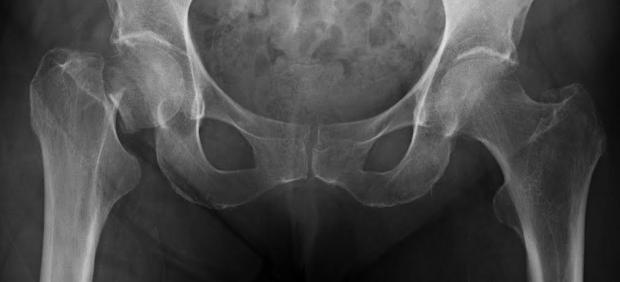

Un grupo de investigadores del Instituto de Investigación Biosanitaria de Granada ha creado un protocolo de detección eficaz para la hipofosfatasia, una enfermedad rara que ataca al correcto funcionamiento de los huesos y que podrían padecer, sin saberlo, cerca de 15.000 personas en España.

La hipofosfatasia, es una trastorno metabólico y hereditario producido «por la falta de mineralización en los huesos y dientes», ha explicado a 20minutos la endocrinóloga pediátrica del Hospitasl Clínuco San Carlos, Olga Pérez.

La sistomatología es muy variable, depende de la «gravedad de la afección», según Pérez. Mayoritariamente consiste en «alteraciones en el esqueleto», explica. Las deformidades en los huesos fácilmente fracturables y la lenta velocidad de crecimiento en niños afectados son algunos de los síntomas de la enfrmedad.